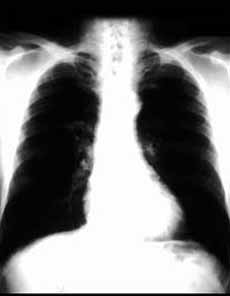

卡肺囊蟲肺炎2.兒童-成人型(現代型)起病較急,開始時乾咳,迅速出現高熱、氣促、發紺,肺部體徵甚少,可有肝脾腫大。從起病到診斷,典型的為1~2周,接受大劑量激素治療者,病程短促,可於4~8天死亡。AIDS患者病程較為緩慢,漸進,先有體重下降、盜汗,淋巴結腫大,全身不適,繼而出現上述呼吸道症狀,可持續數周至數月。未經治療100%死於呼吸衰竭。本病症狀嚴重,但肺部體徵較少,多數患者肺部聽診無異常,部分病人可聞及散在濕囉音。

卡肺囊蟲肺炎2.血氣和肺功能動脈血氣常有低氧血症和呼吸性鹼中毒。肺功能檢查肺活量減低。肺彌散功能(DLCO)低於70%估計值。